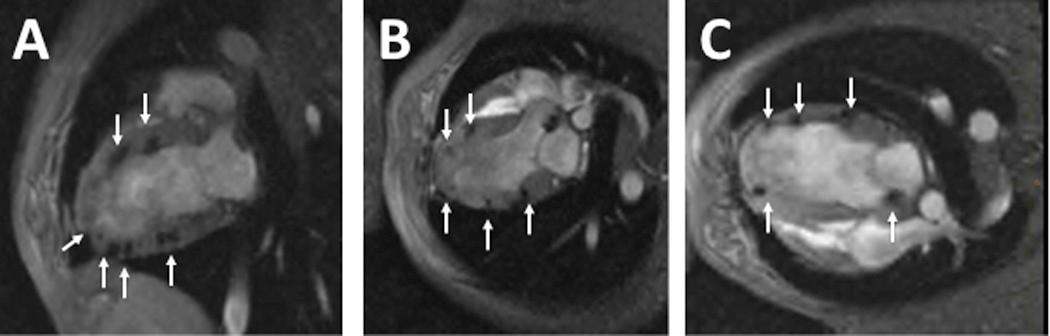

Duchenne muscular dystrophy (DMD) cardiomyopathy patients currently have no therapeutic options. We evaluated catheter-based transendocardial delivery of a recombinant adeno-associated virus (rAAV) expressing a small nuclear U7 RNA (U7smOPT) complementary to specific cis-acting splicing signals. Eliminating specific exons restores the open reading frame resulting in translation of truncated dystrophin protein. To test this approach in a clinically relevant DMD model, golden retriever muscular dystrophy (GRMD) dogs received serotype 6 rAAV-U7smOPT via the intracoronary or transendocardial route. Transendocardial injections were administered with an injection-tipped catheter and fluoroscopic guidance using X-ray fused with magnetic resonance imaging (XFM) roadmaps. Three months after treatment, tissues were analyzed for DNA, RNA, dystrophin protein, and histology. Whereas intracoronary delivery did not result in effective transduction, transendocardial injections, XFM guidance, enabled 30±10 non-overlapping injections per animal. Vector DNA was detectable in all samples tested and ranged from <1 to >3000 vector genome copies per cell. RNA analysis, western blot analysis, and immunohistology demonstrated extensive expression of skipped RNA and dystrophin protein in the treated myocardium. Left ventricular function remained unchanged over a 3-month follow-up. These results demonstrated that effective transendocardial delivery of rAAV-U7smOPT was achieved using XFM. This approach restores an open reading frame for dystrophin in affected dogs and has potential clinical utility.

杜氏肌营养不良症 (DMD) 心肌病患者目前尚无治疗选择。我们评估了经心内膜导管传递表达与特定顺式作用剪接信号互补的小核 U7 RNA(U7smOPT)的重组腺相关病毒 (rAAV)。消除特定外显子会恢复开放阅读框,从而导致截短的肌营养不良蛋白的翻译。为了在临床上相关的 DMD 模型中测试这种方法,金毛寻回猎犬肌营养不良症 (GRMD) 狗通过冠状动脉内或经心内膜途径接受血清型 6 rAAV-U7smOPT。经心内膜注射使用注射尖端导管和 X 射线融合磁共振成像 (XFM) 路线图进行荧光引导。治疗 3 个月后,对组织进行 DNA、RNA、肌营养不良蛋白和组织学分析。虽然冠状动脉内递送未导致有效转导,但经心内膜注射和 XFM 引导使每个动物可进行 30±10 次非重叠注射。所有测试样本均检测到载体 DNA,范围为每个细胞<1 到>3000 个载体基因组拷贝。RNA 分析、western blot 分析和免疫组织化学分析表明,在治疗的心肌中广泛表达了跳过的 RNA 和肌营养不良蛋白。在 3 个月的随访中,左心室功能保持不变。这些结果表明,XFM 实现了 rAAV-U7smOPT 的有效经心内膜传递。这种方法在受影响的狗中恢复了肌营养不良蛋白的开放阅读框,具有潜在的临床应用价值。